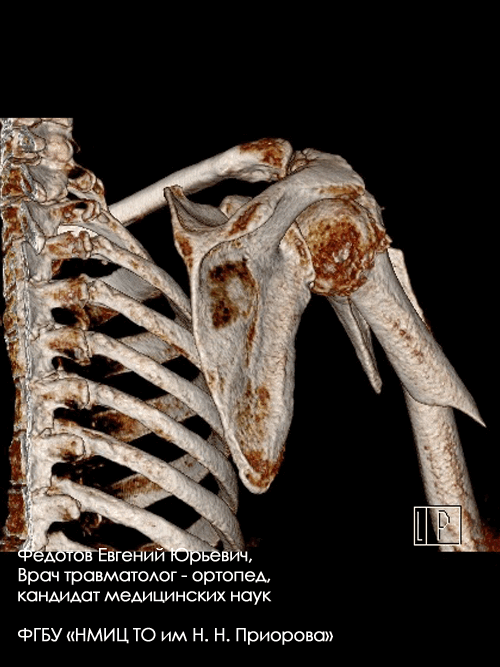

Переломы верхнего отдела плеча (проксимального отдела плечевой кости).

Такие переломы при некорректном лечении могут привести к выраженным нарушениям движений в плечевом суставе, когда пациент элементарно не может достать рукой до головы. Оперативное лечение таких переломов сложно и требует высокой квалификации хирурга и применения современных методик. При соблюдении этих условий в настоящее время можно достичь практически полного восстановления функции плечевого сустава.

Пациентка с очень тяжелым переломом верхнего отдела плечевой кости со значительным смещением отломков.

Рентгенограмма до операции.

Выполнена операция: металлоостеосинтез плечевой кости полиаксиальной пластиной LCP.

Гипсовая повязка после операции не применялась, сразу после операции начата физкультура для суставов и мышц конечности.

Результат через 1,5 мес. после операции.

Конечность совершенно не отличается от здоровой, рубца на месте операции не видно (накладывался косметический шов). Функция плечевого сустава полностью восстановлена.